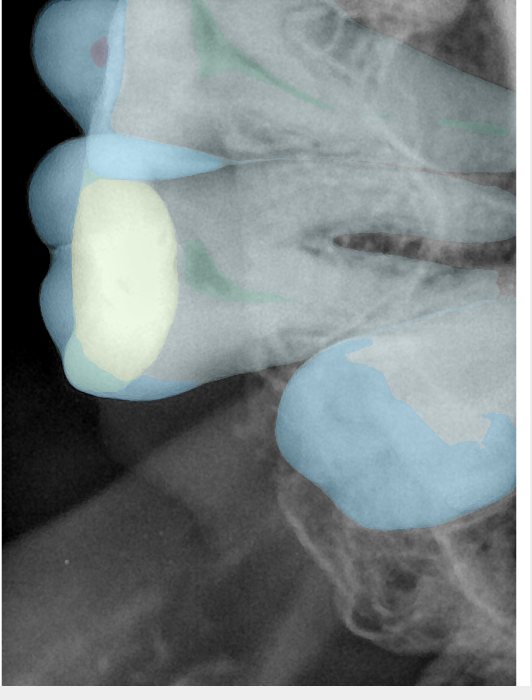

CR/DR 牙齿分割阶段记录

当前进展

- 完成了 CR/DR 牙齿相关分割训练

- 当前结果已经达到阶段预期,但仍有细节问题需要继续处理

相关测试

遇到的问题

- 训练过程中出现过 mask 下移问题

- 部分结果会出现 box 填充异常

- mask 边缘仍然有比较明显的锯齿感

参考

第二版算法问题测试

| 第一版 | 第二版 | 是否解决 | |

|---|---|---|---|

![]() | ![]() ![]() 边角识别有问题 龋齿识别不全 牙髓识别不全 | ![]() | 解决 |

![]() | ![]() 边角识别有问题 识别信息有误 自查(牙冠识别不全) | ![]() | 解决 |

![]() | ![]() ![]() 边角识别有误 大范围填充识别遗漏 | ![]() | 解决 |

![]() | ![]() 识别信息不全 | ![]() | 解决 |

![]() | ![]() ![]() 边角问题 牙胶识别不全 牙冠识别不全 | ![]() | 解决 |

![]() 换图片 | ![]() | ![]() 牙冠部分稍微白了一些就识别成小范围修补,部分判断异常 | 部分解决,修复类略敏感,牙冠部分稍微白了一些就识别成小范围修补,部分判断异常。 |

![]() | ![]() ![]() 牙冠识别不全 牙髓不全 根尖炎龋齿识别有误 | ![]() | 解决 |

![]() | ![]() | ![]() | 解决 |

![]() 换图片 | ![]() | ![]() | 解决 |

![]() | ![]() 牙冠识别有误 | ![]() | 解决 |

![]() 换图片 | ![]() ![]() 边角识别有误 | ![]() 修复类敏感 | 部分解决,图像过白,导致修复类判断异常。 |

![]() 换图片 | ![]() 牙冠识别不全 | ![]() 修复类敏感 | 部分解决,图像过白,导致修复类判断异常 |

结论:修复类出现了不鲁棒的情况,后续需要加入轮廓的扩充数据进行增强。